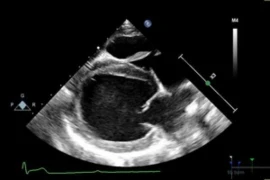

This e-learning course provides veterinarians with fundamental knowledge of veterinary cardiology. It covers the anatomy and physiology of the heart, common congenital abnormalities, diagnostic methods such as auscultation, ECG and reading chest radiographs. The course is practice-oriented and ideal for both refreshing existing knowledge and as an introduction to cardiac examination and treatment in small animal practice. Finally we will also dive into the basics of ultrasonography of the heart.

• Ultrasonography of the Heart - Basics. 2 September 2025, 8pm CEST